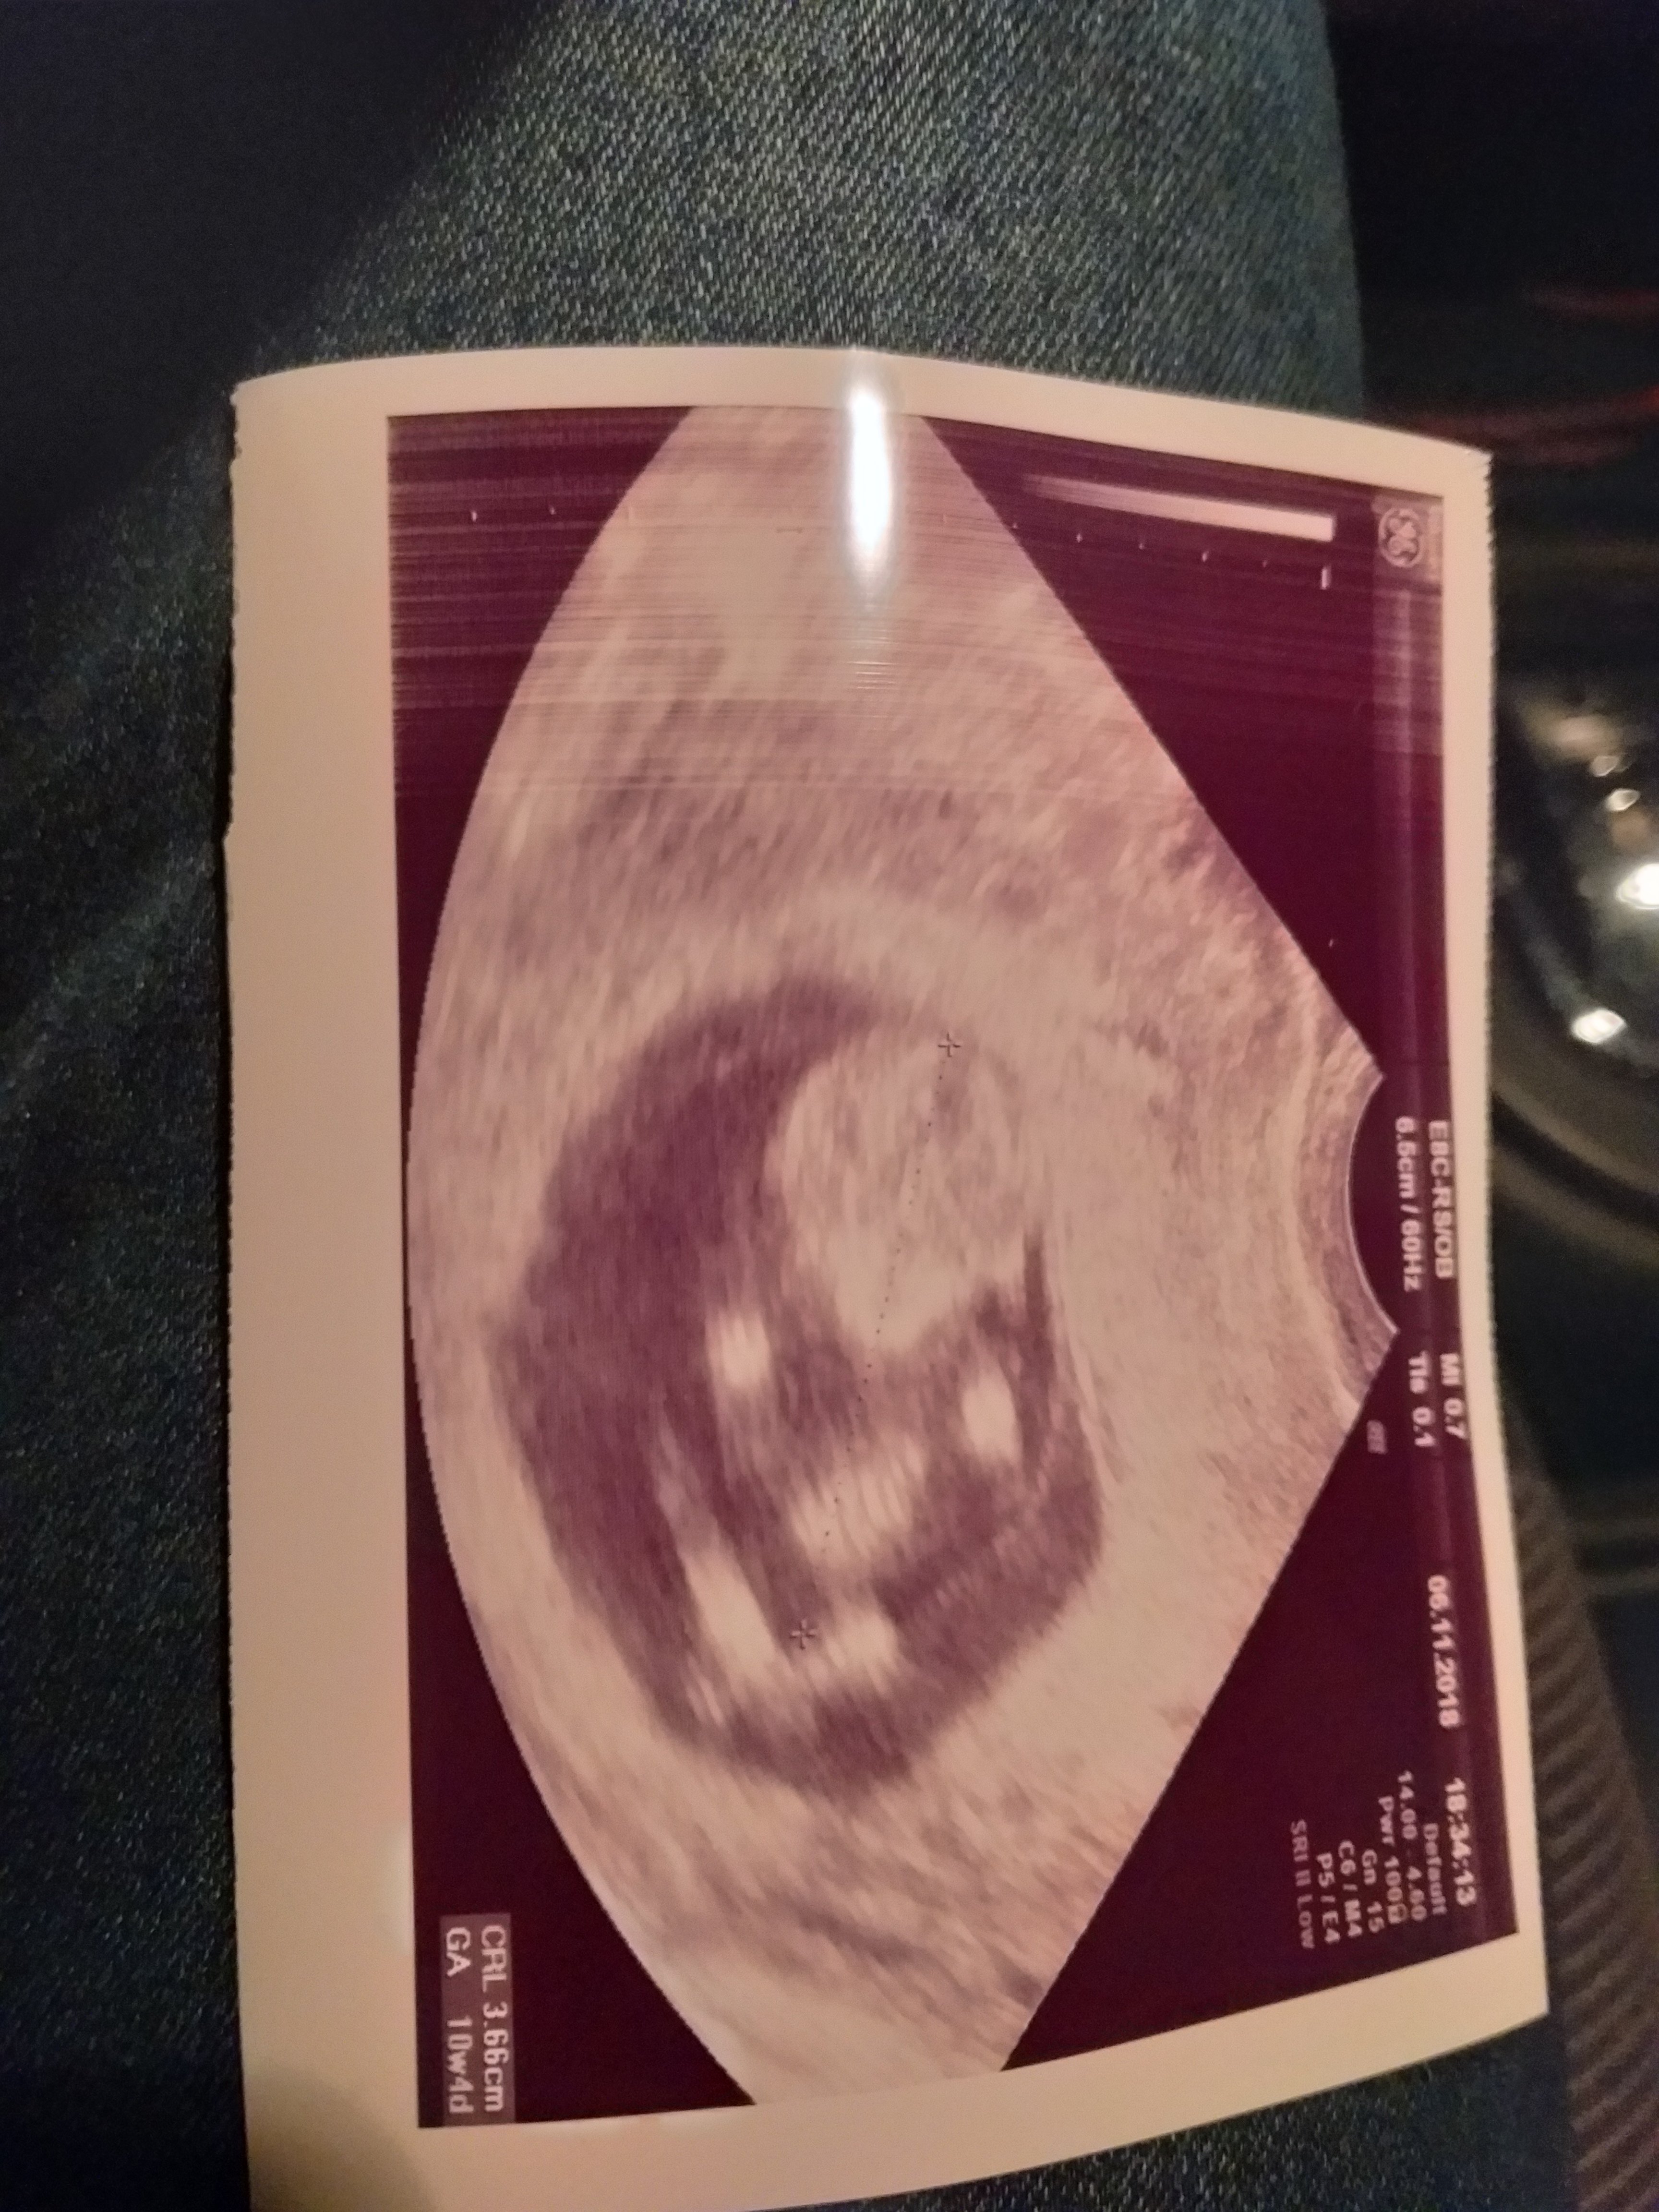

10+3Jeju ale slodkie zdjecie [emoji7][emoji7][emoji7] ciesze sie ze wszystko dobrze [emoji7]

Śliczności :-*Melduję się, bobas fika, ma 3,5 cm i jest mega ruchliwy, wrzucam zdjęcie mam nadzieję że się rozczytacie, te największe to głowa z przodu, z boku rączki i na dole nóżki hihiZobacz załącznik 914252